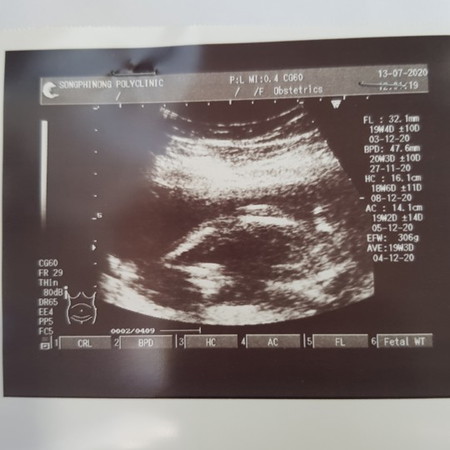

ซาวด์ตอน5เดือนคะท้องแรก หมอบอกว่ายังเห็นไม่ชัดเจนเลยว่าเพศอะไร มีแม่ๆท่านไหนมองออกบ้างมั้ยคะ เราเองมองไม่รุ้เรื่องเลยคะ😅

ของเราคล้ายๆแบบนี้ เป็นผญ.อ่ะค่ะ ไม่ชัวร์นะคะ อายุครรภ์มากกว่านี้อาจมีโผล่มาอีก